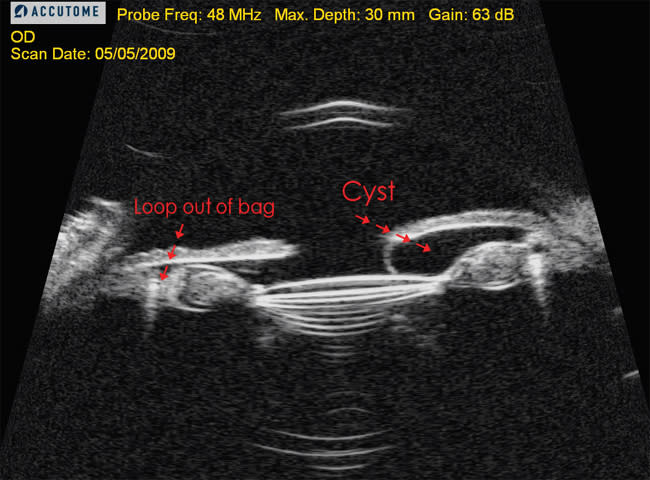

The device is said to accommodate a range of demands, including angle evaluation, measuring sulcus-to-sulcus distance for sulcus-supported IOLs, and imaging of the iris and ciliary body cysts or tumors. One of the primary uses for UBMs in Dr. Fram's and Dr. Masket's office is evaluating pathology caused by malpositioned PCIOLs.

Accutome's UBM Plus scans high-res images of the anterior segment, as shown here.